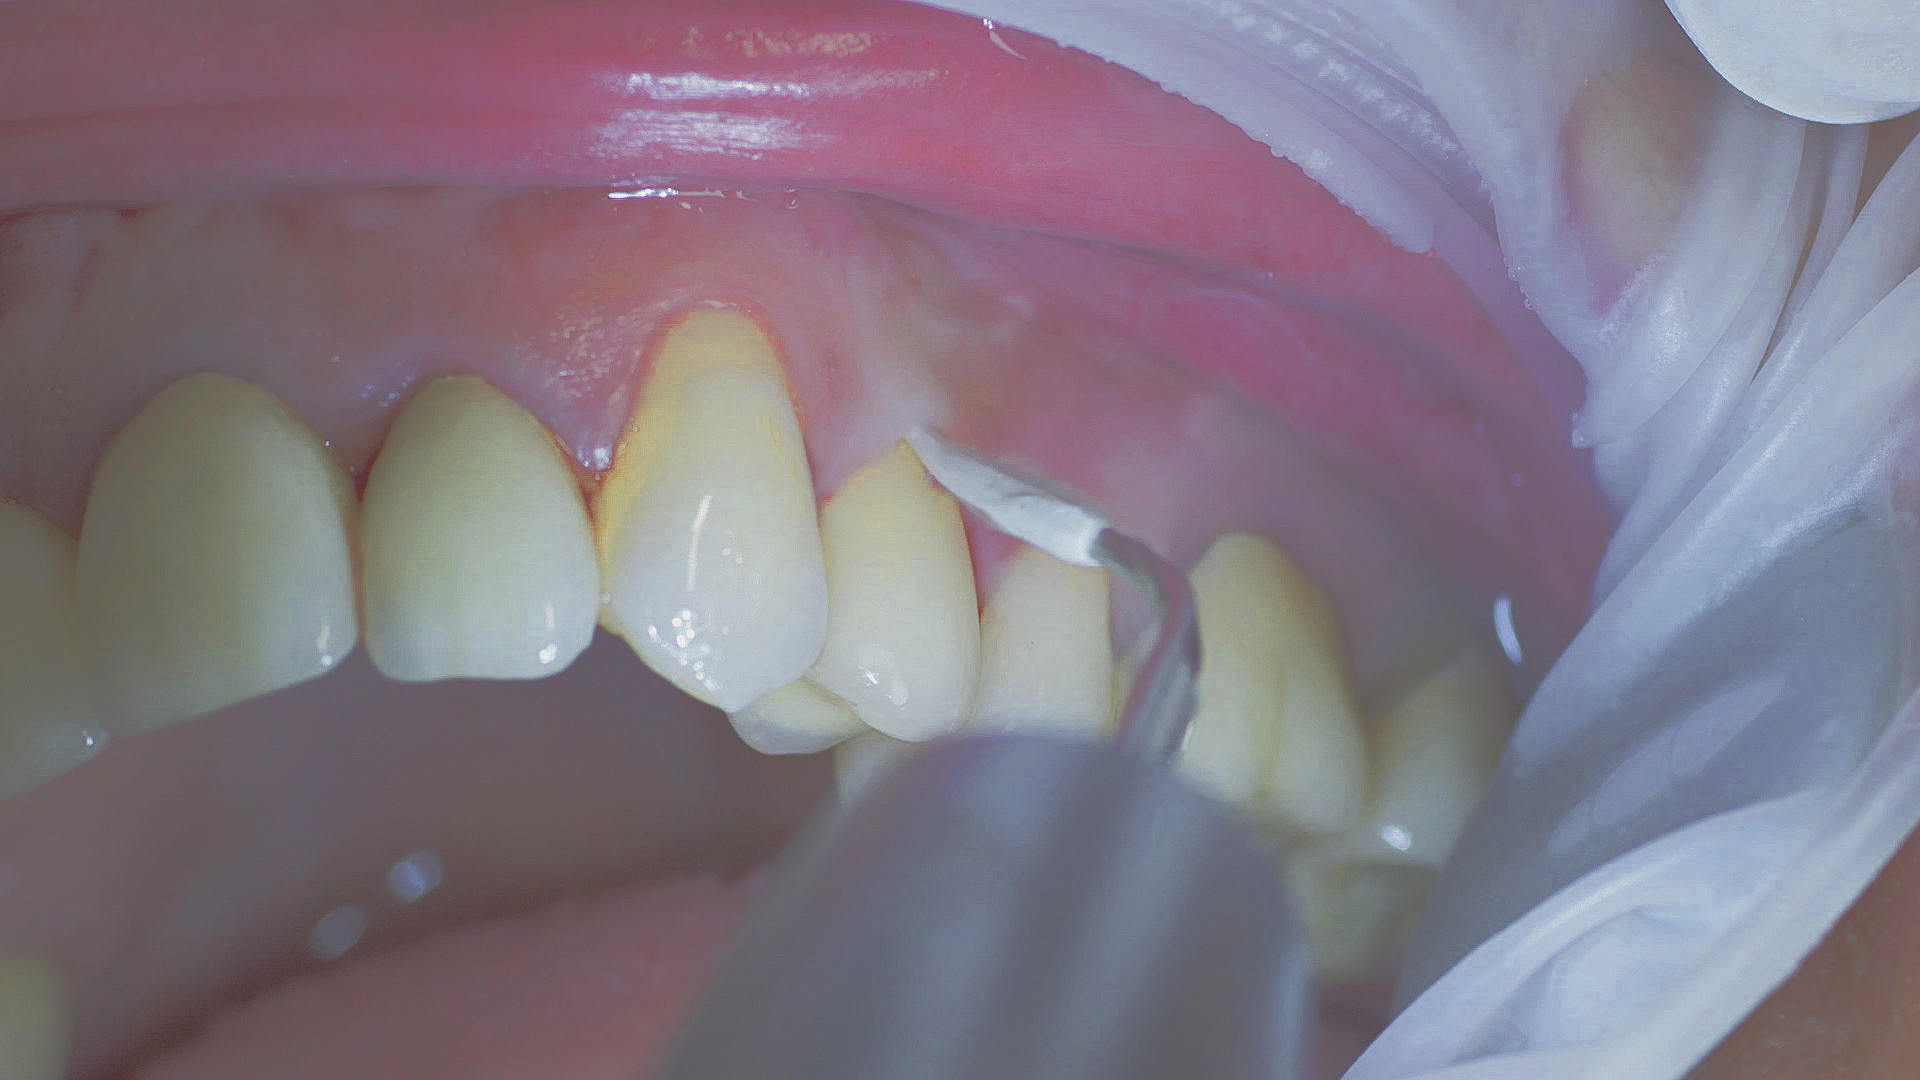

Where necessary, initial periodontal treatment is carried out. First, professional tooth cleaning establishes healthy gingival conditions. In this procedure, calculus (Fig. 1) and biofilm (Fig. 2) are removed as far as the gingival sulcus. In combination with careful instruction on oral hygiene, this gives the patient the basis for long-term freedom from inflammation.15